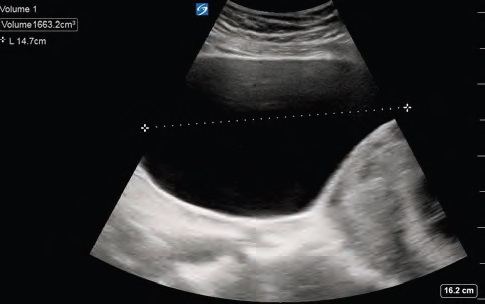

A 40-year-old female at 11 weeks, five days gestation presented to the emergency department (ED) with concern for lower abdominal pressure and inability to fully empty her bladder. She had urinary dribbling when standing and leaning forward. She denied fevers, back pain, saddle anesthesia, numbness, or weakness in the extremities. She reported no history of prior back surgeries, intravenous drug use, recent falls, trauma, or known inciting event. There was no vaginal bleeding or vaginal discharge. Transvaginal ultrasound (TVUS) performed in the outpatient setting a couple of weeks prior to presentation confirmed an intrauterine pregnancy (IUP) with a retroverted uterus. Straight catheterization resulted in approximately 1,500 mL of clear urine output and relief of symptoms. Urinalysis showed no evidence of infection, and the patient was discharged home.

Incarcerated gravid uterus is a rare diagnosis with an estimated incidence of one in 3,000 to one in 10,000 pregnancies.1-3 It most commonly occurs in patients with a retroverted uterus during weeks 10 through 16 of pregnancy. As the uterus grows, it can spontaneously correct; however, if the uterine fundus remains in the pelvis it can become trapped against the sacral promontory while the cervix is trapped against the pubic symphysis.1,4 Approximately 15 to 20 percent of all pregnancies occur in a retroverted uterine position, however only a rare minority of those pregnancies lead to IGU.1,5

Risk factors include prior abdominal surgeries, history of pelvic inflammatory disease, or prior history of uterine incarceration.6 IGU can be identified via history and physical, pelvic examination, or MRI. Alternatively, ultrasound can be utilized as a diagnostic modality. Transabdominal ultrasound is more helpful for IGU diagnosis than TVUS as the transabdominal approach allows for better visualization of the cervix in relation to the uterus.5,7 Since IGU is a rare presentation, the literature primarily consists of case reports and case series. Treatment options include Foley catheterization until the uterus spontaneously reduces and adopts a normal vertex presentation, having the mother adopt a knee-to-chest position, or manual reduction with appropriate pain control. More invasive techniques such as colonoscopic or laparoscopic reduction have been described.1,7